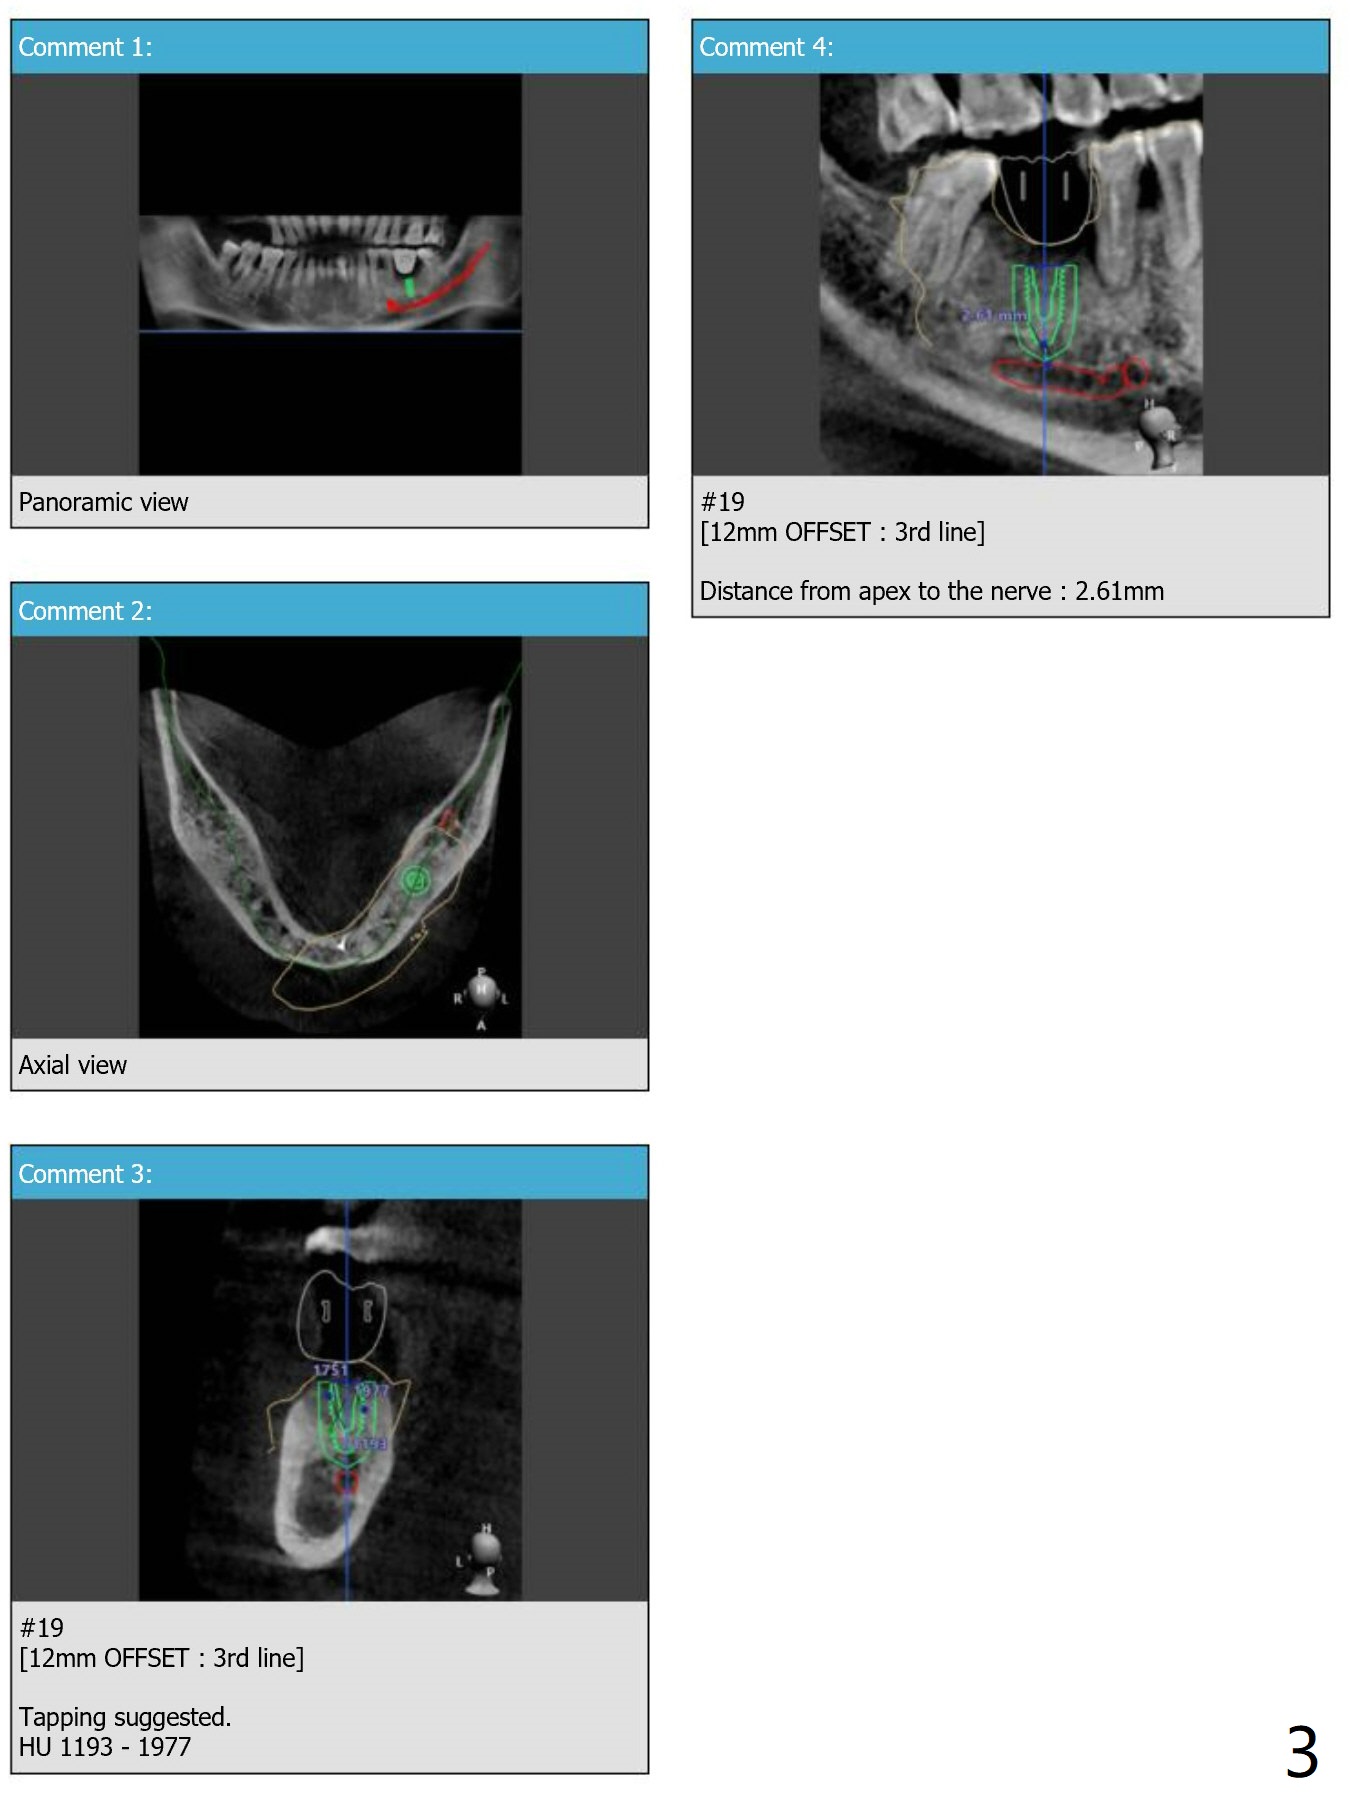

12 mm Offset at #19

Hi, Jennifer: Out of curiosity, which factor decides o use 12 mm offset?  Because of the thick gingiva?  With 12 mm offset, pointed drill appears to go down all the way.  Without offset, pointed drill goes to the first line (for example JY Lee)?  Thanks.

There're several reasons for raising the level of the metal sleeve so called offset. And like you said, thick soft tissue could be one reason for that. When the interdental space is narrow due to the tight contact we raise the level as well.

And for the point drill, you do not have to worry about the line. Because of the tapered part of the drill, you can drill all the way down until it naturally meets the bone and stops.